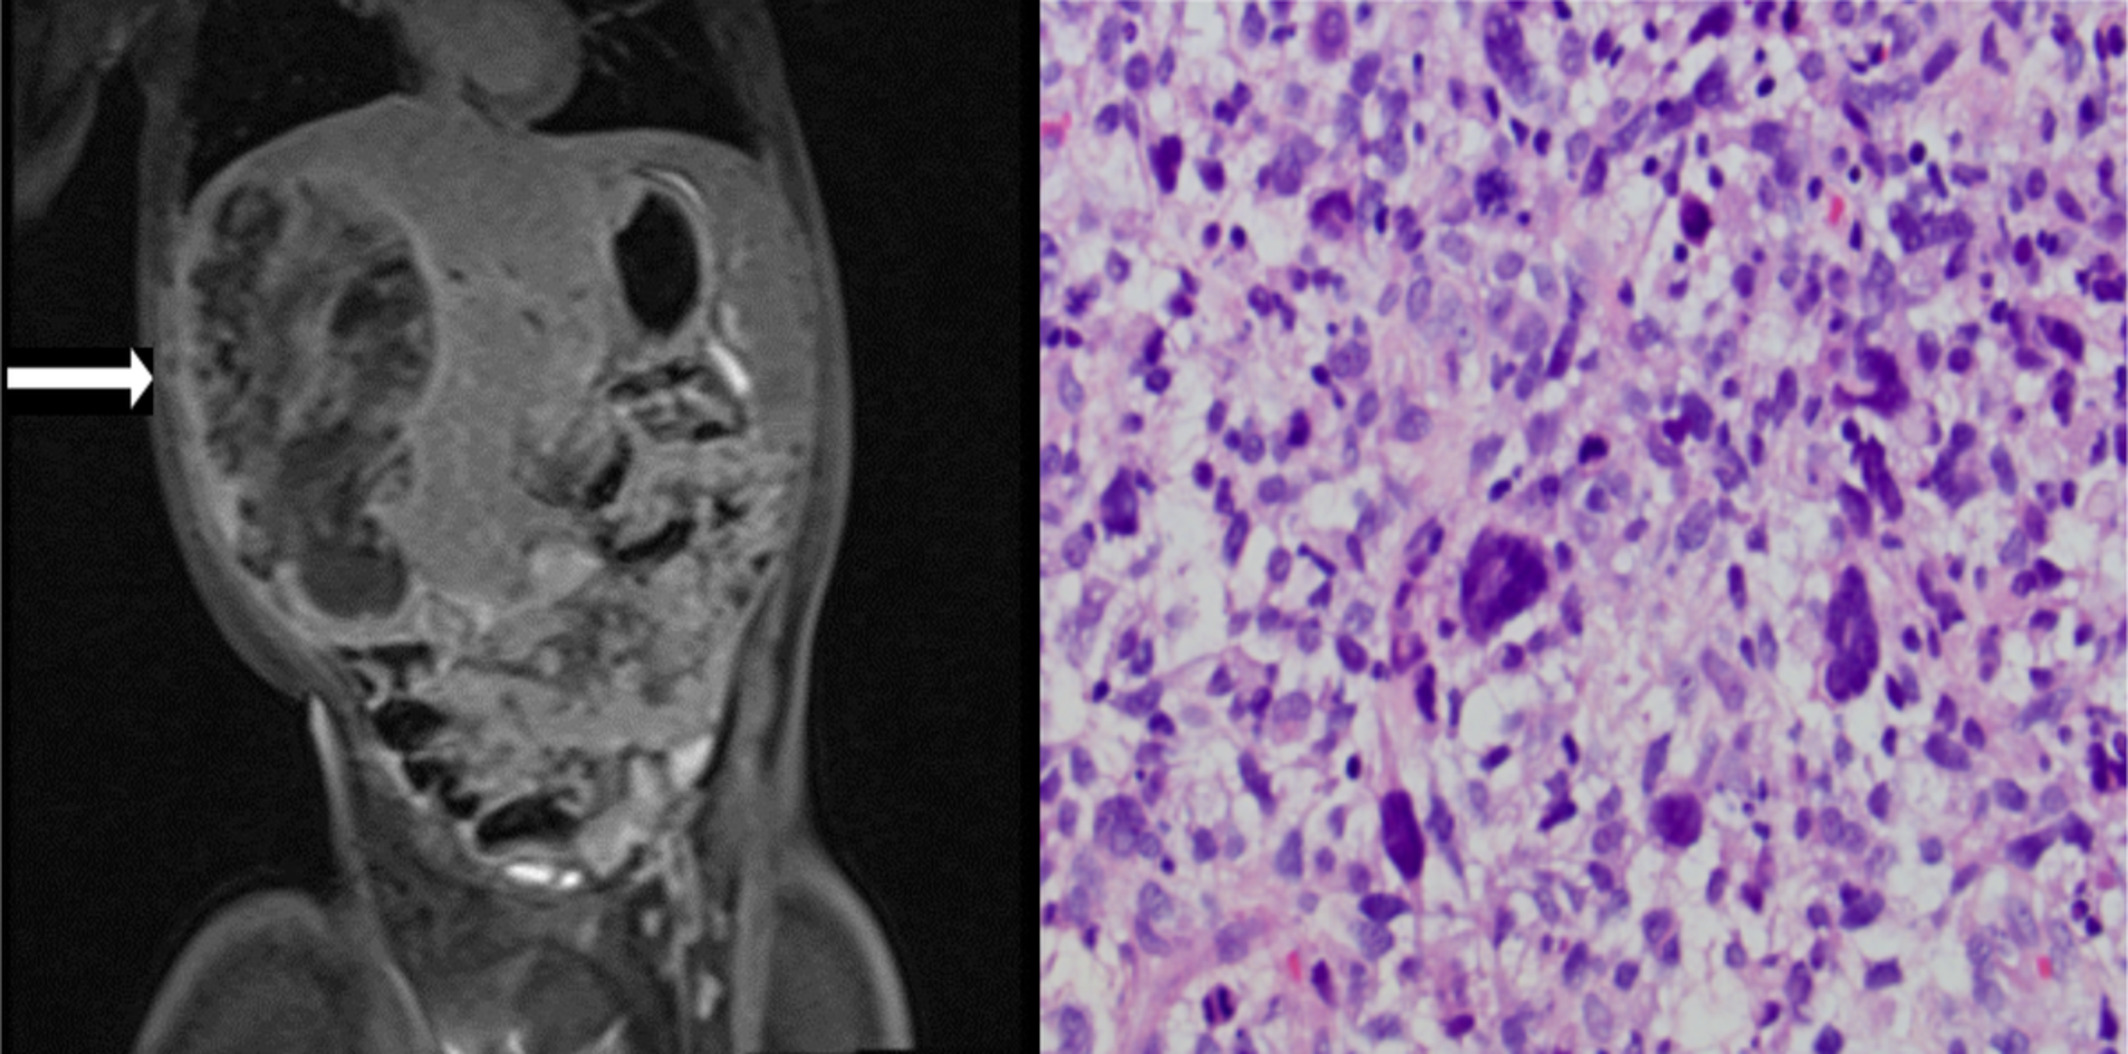

Embryonal sarcoma of the liver in a girl with Cockayne syndrome

The first reported malignancy associated with Cockayne syndrome.